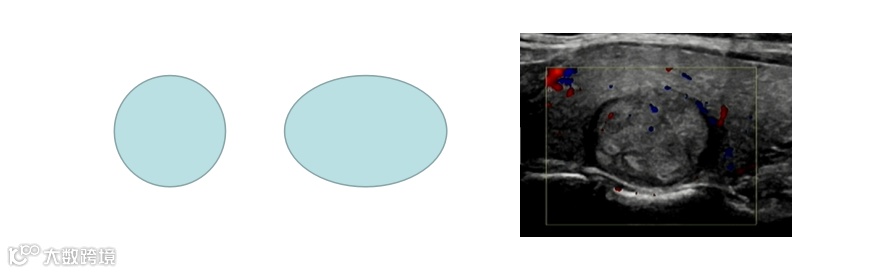

怎么判断结节的良性和恶性??

“以貌取结”&FNA(细针抽吸活检)

良性结节图

恶性结节图